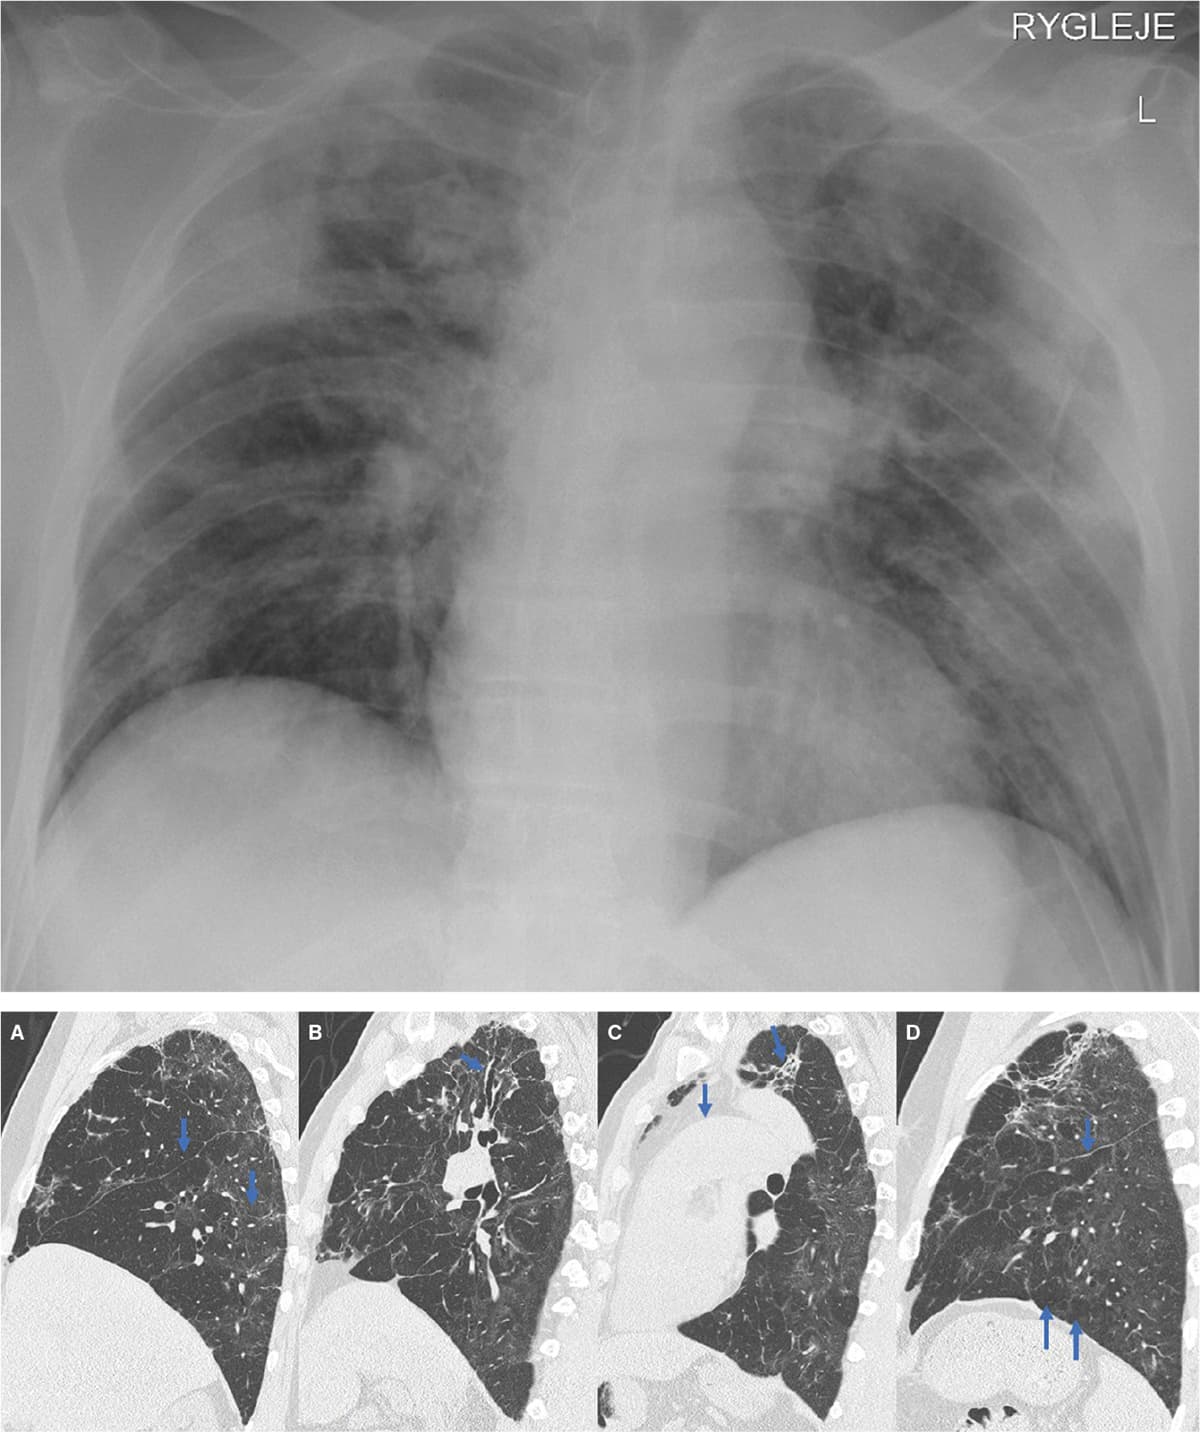

Billederne viser status før indlæggelsen på et intensivafsnit og tre måneder efter udskrivelsen hos en af de første respiratorkrævende patienter med COVID-19 i Danmark. Det første billede er et røntgenbillede af thorax taget med patienten i rygleje, og de sidste fire billeder er high resolution-CT-billeder i sagitalsnit set i et lungevindue.

De tidligere infiltrativt prægede områder er erstattet af udbredte, dels matglasprægede (markeret med pil på A) og dels fibrotisk/cikatricielt udseende områder (markeret med pil på C). Tidligere upåvirket lungevæv fremstår nu hyperekspanderet (formentlig kompensatorisk) (markeret med pil på D) og med fortykkede interlobulære septae og uregelmæssige fissurer (markeret med pile på A og D). Tidligere påviste traktionsbronkiektasier persisterer perifert og centralt (markeret med pil på B). Generelt ses der ikke airtrapping.

Der er breddeøget truncus pulmonalis (markeret med pil på C) som tegn på mulig pulmonal hypertension.